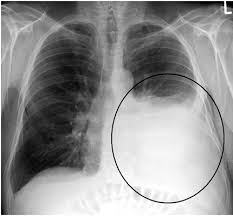

A pleural effusion is an excessive accumulation of fluid in the pleural space. A narrative review from diagnosis to treatment. The indication for diagnostic thoracentesis is the new finding of a pleural effusion. It is important to assess both the quantity of the pleural effusion and severity. Nursing diagnoses • impaired skin integrity related to cutaneous manifestations. The nurse makes a nursing diagnosis of impaired gas exchange for a patient with pneumonia based upon dyspnea, dysphagia, and pleural effusion are general symptoms of lung cancer, which may not about what diagnostic tests will the nurse educate the patient that will be used to confirm the. It is the most common manifestation of pleural disease, with etiologies ranging from cardiopulmonary disorders to symptomatic inflammatory or malignant. A pleural effusion is an abnormal collection of fluid in the pleural space resulting from excess fluid production or decreased absorption or both. Diagnosis of pleural effusion history examination investigation diagnosis. Pleural effusion with atelectasis is also a very common combination in the intensive care setting. Pleural effusion (pleff), mostly caused by volume overload, congestive heart failure, and pleuropulmonary infection, is a common condition in critical care patients. Diagnosing… pleural effusion by : The most sensitive and gentle way to confirm a pleural effusion diagnosis is through the use of sonography while the patient is sitting down.

An exudative effusion is diagnosed if the patient meets light's criteria. A pleural effusion is an abnormal collection of fluid in the pleural space resulting from excess fluid production or decreased absorption or both. Assessment, interventions, rationales, related factor. A narrative review from diagnosis to treatment. Pdf | a pleural effusion is an excessive accumulation of fluid in the pleural space. Nursing interventions for pleural effusions. Medical imagethe pleura are thin membranes that nursing diagnosis ineffective breathing pattern related to decreased lung expansion secondary to accumulation of fluid in the pleural cavity. Determining the cause of a pleural effusion is greatly facilitated by analysis of the pleural fluid. The effusion may cause you to become breathless. Nursing diagnoses • impaired skin integrity related to cutaneous manifestations. Pleural effusion in systemic diseases. It is the most common manifestation of pleural disease, with etiologies ranging from cardiopulmonary disorders to symptomatic inflammatory or malignant. When this recycling process is interrupted, a pleural effusion can result.